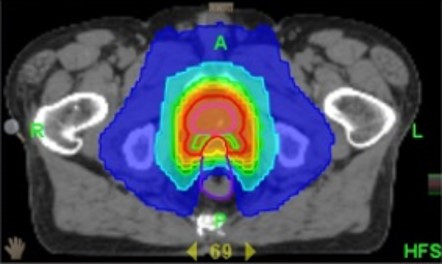

■放射線治療(外照射療法): 外部から放射線を照射し、がんを死滅させる治療法です。現在は、高精度放射線治療である強度変調放射線治療(IMRT)が標準的な治療法とされています。IMRTでは正常組織の被曝を最小限にしつつ、がん組織に放射線を集中的に照射することが可能です。